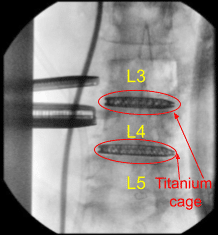

Intraoperative X-ray

AP and lateral radiographs indicated excellent cage positioning, restoration of lordosis, and indirect decompression throughout. Accordingly, the L3-L4 cage was released from the cage inserter. The area was copiously irrigated with antibiotic impregnated saline and packed with Surgiflo hemostatic matrix product.

Once we were certain that the disc space was prepared for arthrodesis, an 8 x 55 x 22 mm lordotic 3D printed titanium cage was selected from the NuVasive tray and impacted into place at the L4-L5 disc space. Excellent indirect decompression and completion of L4 neuroplasty was seen with separation of the L4 and L5 vertebral bodies.

Serial bullet trials were impacted into the L3-L4 disc space to complete an indirect decompression and neuroplasty of the exiting L3 nerve roots. The bony endplates were then aggressively prepared with a ring curette following withdrawal of the bullet paddles. An 8 x 50 x 22 mm lordotic CoRoent titanium cage from the NuVasive tray was then directly impacted into L3-L4 disc space to complete the arthrodesis.